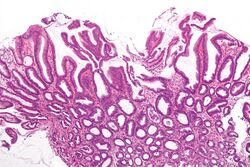

Reactive gastropathy - intermed mag.jpg

Micrograph of a reactive gastropathy. H&E stain.

Reactive gastropathy, is characterized histologically by:[2]

- Foveolar hyperplasia (black arrow), as a tortuosity in the "neck" region of the gastric glands.

- Scant or minimal inflammatory cells (white arrow), i.e. lack of large numbers of neutrophils and plasma cells..

- Smooth muscle hyperplasia in the lamina propria (in black oval).

The diagnosis is by examination of tissue, e.g. a stomach biopsy.